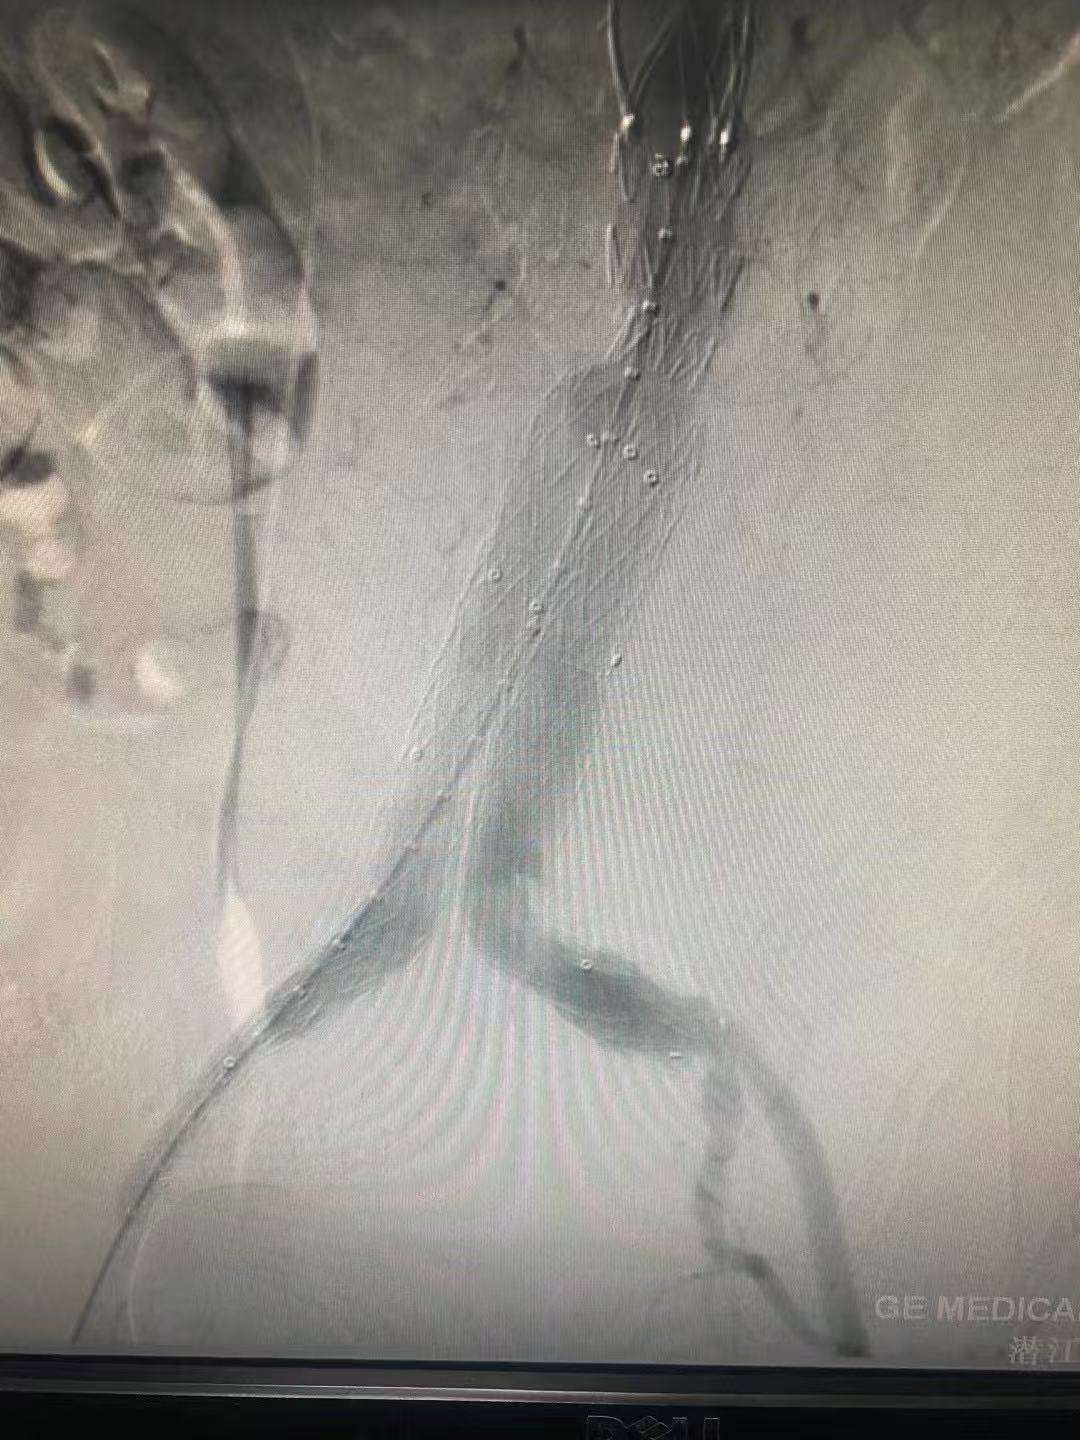

经过最短的术前准备,在介入团队的缜密手术操作和麻醉团队的持续麻醉保障下,顺利为李婆婆植入了支架。术后,李婆婆腹部跳动的包块消失了,标志着这颗威胁着她的「不定时炸弹」成功拆除,随即返回病房接受后续治疗。术后通过 CTA 复查确认,李婆婆的腹主动脉瘤瘤口已完全闭合,血流通畅,恢复情况良好,一家人悬着的心终于落地。

支架植入及球囊扩张形成后